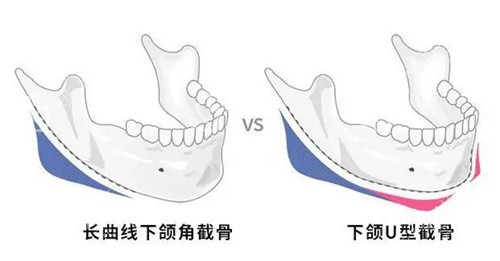

下颌角处理的独到之处

他倾向保留生理性角度的自然做法。并非一味追求极致V脸结果。使术后侧面轮廓线条流畅真实。做到“显小不显假”的自然感。